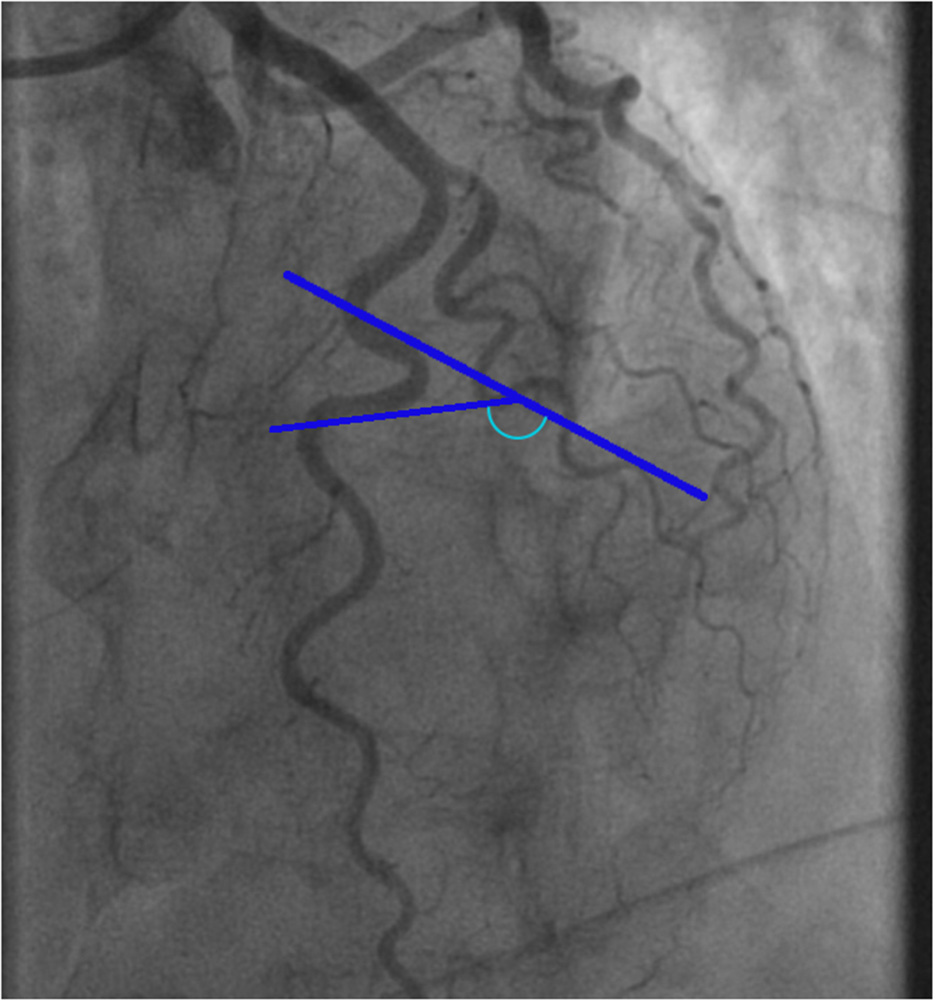

Since physiologic measurements during CFT were performed in the LAD artery, we also evaluated coronary tortuosity in the LAD artery. For the measurement of tortuosity, the left anterior oblique (LAO) 45-cranial 30° and the right anterior oblique (RAO) 30-cranial 30° views were used. The view after nitroglycerin infusion was primarily used, which was usually the LAO 45-cranial 30° view. Measurements of the other views were applied to estimate the angles of curvatures that were not entirely visualized on the LAO view. Measurements were performed at end-diastole as visualized in Figure 1. To quantify the severity of coronary tortuosity, the classification set up by Eleid et al. (7) was used. Mild tortuosity was defined as the presence of ≥3 consecutive curvatures of 45– 90° in the LAD artery or ≥3 consecutive curvatures of 90–180° in a diagonal of the LAD artery. Moderate tortuosity was defined as the presence of ≥3 consecutive curvatures of 90–180° in the LAD artery, and severe tortuosity was defined as the presence of ≥2 consecutive curvatures of ≥180° in the LAD artery. Patients who did not meet any of these criteria were defined as no tortuosity. The LAD artery were also examined on several additional markers of tortuosity (Table 1), including the S-curve sign, the intravessel symmetry sign, and the corkscrew sign, as described in the study by Ciurică et al. (16) Additionally, we considered the number of curvatures in the LAD artery as another marker of tortuosity (Figure 2).

Figure 1

Example of a tortuosity measurement of the left anterior descending artery. The blue marked angle defines the angle of the curvature surrounded by blue lines.